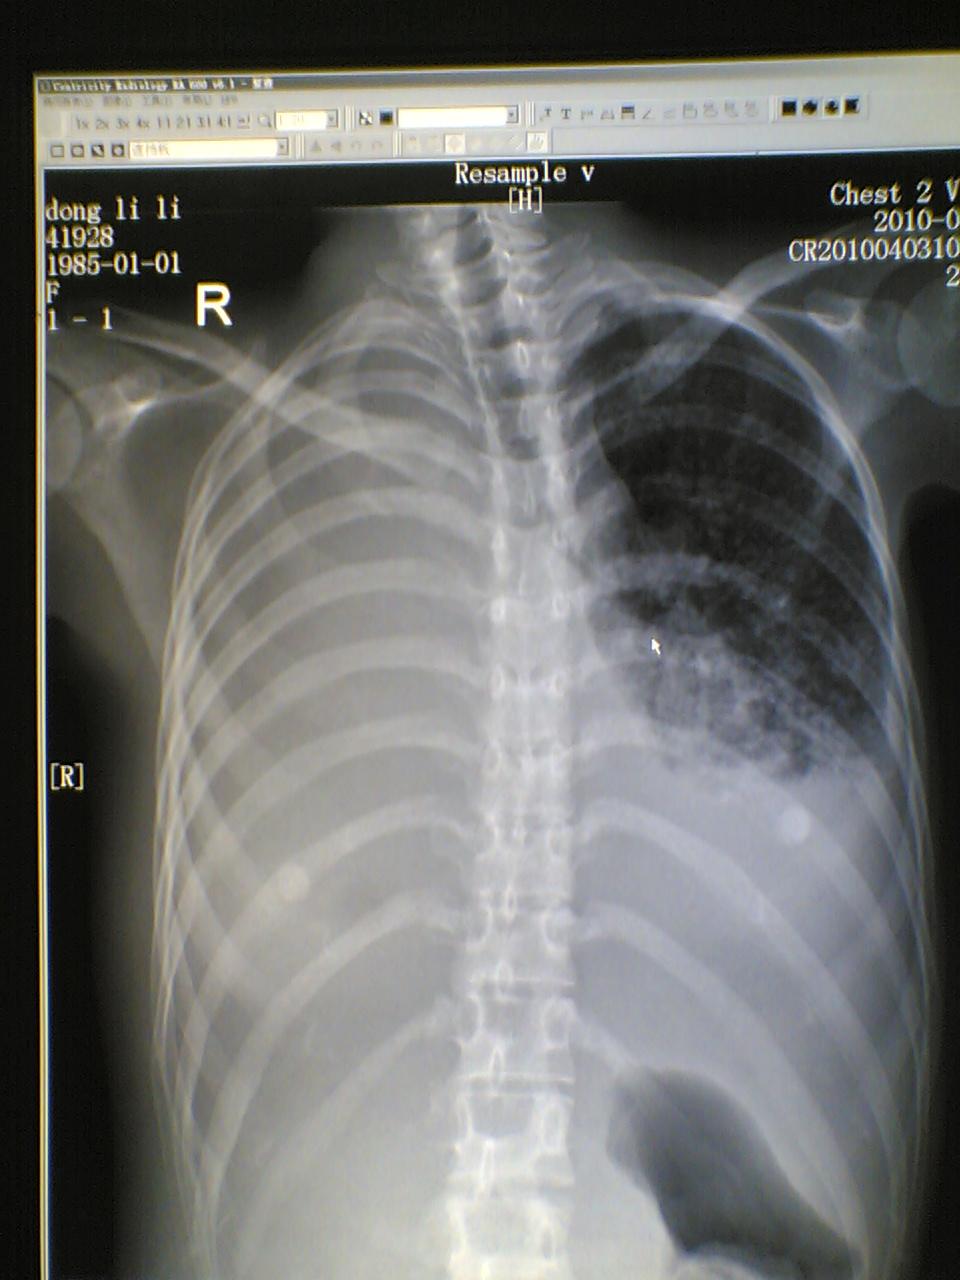

标题: X7068:女,25岁,自觉胸部气紧不适一年。请老师指教。

左肺结核病灶?肺泡癌?

考虑左肺结核,右侧肺毁损;左侧胸腔积液。

考虑左肺结核,左侧胸腔积液。右侧大量胸腔积液并全肺叶不张。

右肺不开窗,纵隔无移位,估计是积液与不张并存,结合患者年龄及病史考虑支气管内膜结核并左肺播散。

病人年轻,病史较长1年,还是考虑慢性病 结核了, 侧位看上肺也有片絮状病变,当然要做个ct ,估计右侧为实变和胸腔积液